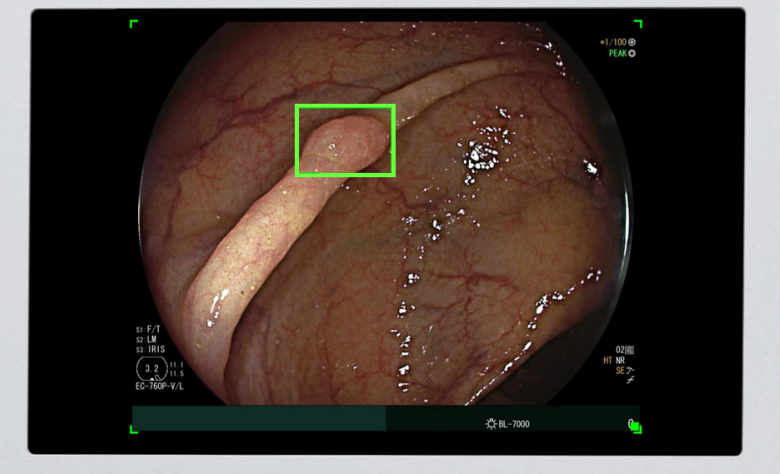

Manufactured and marketed by Medtronic, the device is meant to be a second set of eyes. After being attached to an endoscope video, the deep learning computer pinpoints potential polyps.

The AI processes colonoscopy images and superimposes a green square over suspected lesions.